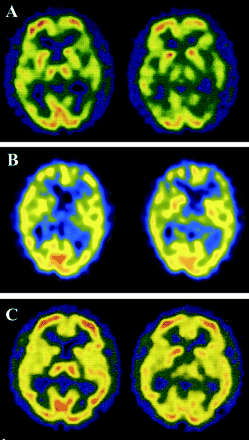

神经系统检查4个月后开始显示含糊不清构音障碍,左侧上、下肢的笨拙,痴呆。EEG是正常的。14-3-3蛋白的CSF水平是模棱两可的。MRI显示gyriform hyperintensity双边额、颞、顶叶、枕叶皮质醉酒驾车。正的大脑显示弥漫性双边丘脑皮层代谢减退。库贾氏症被怀疑作为早期诊断。

平方毫米的情况下丘脑的形式,发病年龄范围从30到71年,临床过程的持续时间从13到73个月(见表1)。临床表现包括精神病症状,痴呆,小脑性共济失调、失眠、和自主失败(见表1)。至于FFI的突出特点和SFI,失眠在只有一个病人(病人4),和自主症状被发现在三个病人(病人4、5、7)。脑电图显示没有PSWCs除了一位病人(病人6)显示PSWCs很晚阶段(见表2)。这些特性与先前报道的患者数目丘脑3或者你以后。8、10脑部核磁共振成像,包括醉酒驾车,几乎是正常的平方毫米丘脑的患者除了脑萎缩或白质后期的变化(见表2)。这些功能与以前的报道相一致SFI患者。8、10在我们的研究中,两个病人检测CSF 14-3-3蛋白,一个是积极的,另一个是模棱两可(见表2)。在文献中,据我们所知,有报道称,4平方毫米丘脑sCJD患者检查脑脊液14-3-3蛋白:考试是积极的6和负三。7、8考虑这些报道与我们的结果,我们不能得出结论,CSF 14-3-3蛋白诊断平方毫米丘脑sCJD足够敏感。最初的临床诊断,进行性核上的麻痹(PSP),脊髓小脑的变性(SCD),或广告一直怀疑(见表1),表示相当困难的临床诊断平方毫米丘脑的形式。然而,我们回顾CBF-SPECT研究显示特征的结果减少CBF的双边丘脑和大脑皮层的相对早期阶段(见表2)。在以前的报告CBF-SPECT研究库贾氏症病人,减少CBF的目视检查发现大脑皮层不同区域的但不是在丘脑。26日,27日没有关于CBF-SPECT平方毫米丘脑sCJD报告。在摄影的研究中,丘脑和大脑皮层的代谢减退患者SFI报道10或者在某些FFI患者。28、29CBF和丘脑葡萄糖代谢相对保存在广告。30.在PSP,显著减少葡萄糖代谢不是丘脑中发现,而是在额叶皮层通过地区检测到/枕的代谢率。31日多系统萎缩,零星的SCD的表型,减少丘脑CBF的报道;然而,显著减少CBF还检测到的背壳。32我们的患者数目丘脑sCJD没有CBF的壳(见减少图2 b)。我们的研究结果清楚地表明,减少双边丘脑CBF以及代谢减退,与他们的保护壳,将是一个特别有用的诊断为平方毫米丘脑sCJD标记。

有趣的是,在病人与平方毫米(corticothalamic)形式(病人3)相结合,两平方毫米的神经影像学研究显示功能皮层和丘脑的形式,也就是说,hyperintense信号在醉酒驾车和丘脑皮层代谢减退摄影(见表2),与这个病人的病理结果一致。

结果:8例病理分为皮质(n = 2)、丘脑(n = 5),并结合(corticothalamic) (n = 1)的形式。皮质的形式被迟发性的特点,慢慢进步的痴呆,皮质hyperintensity信号diffusion-weighted大脑成像(驾车),和CSF 14-3-3蛋白水平升高。丘脑的形式显示各种神经系统症状包括痴呆、共济失调,锥体和锥体束外的迹象出现在各种年龄和疾病持续时间相对较长。脑电图特点和MRI异常几乎缺席。然而,所有四个患者对脑血流量(CBF)研究使用SPECT显示减少的CBF丘脑和大脑皮层。合并后的表单功能的皮层和丘脑的形式,显示皮质hyperintensity信号醉酒驾车和丘脑的代谢减退18F] 2-fluoro-2-deoxy-d-glucose宠物。